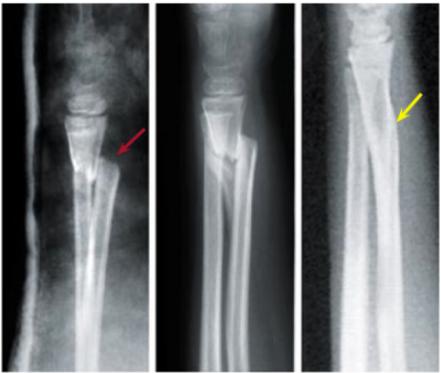

Femoral Shaft Displacement Example

“We accept it in children, but in adults we don’t”